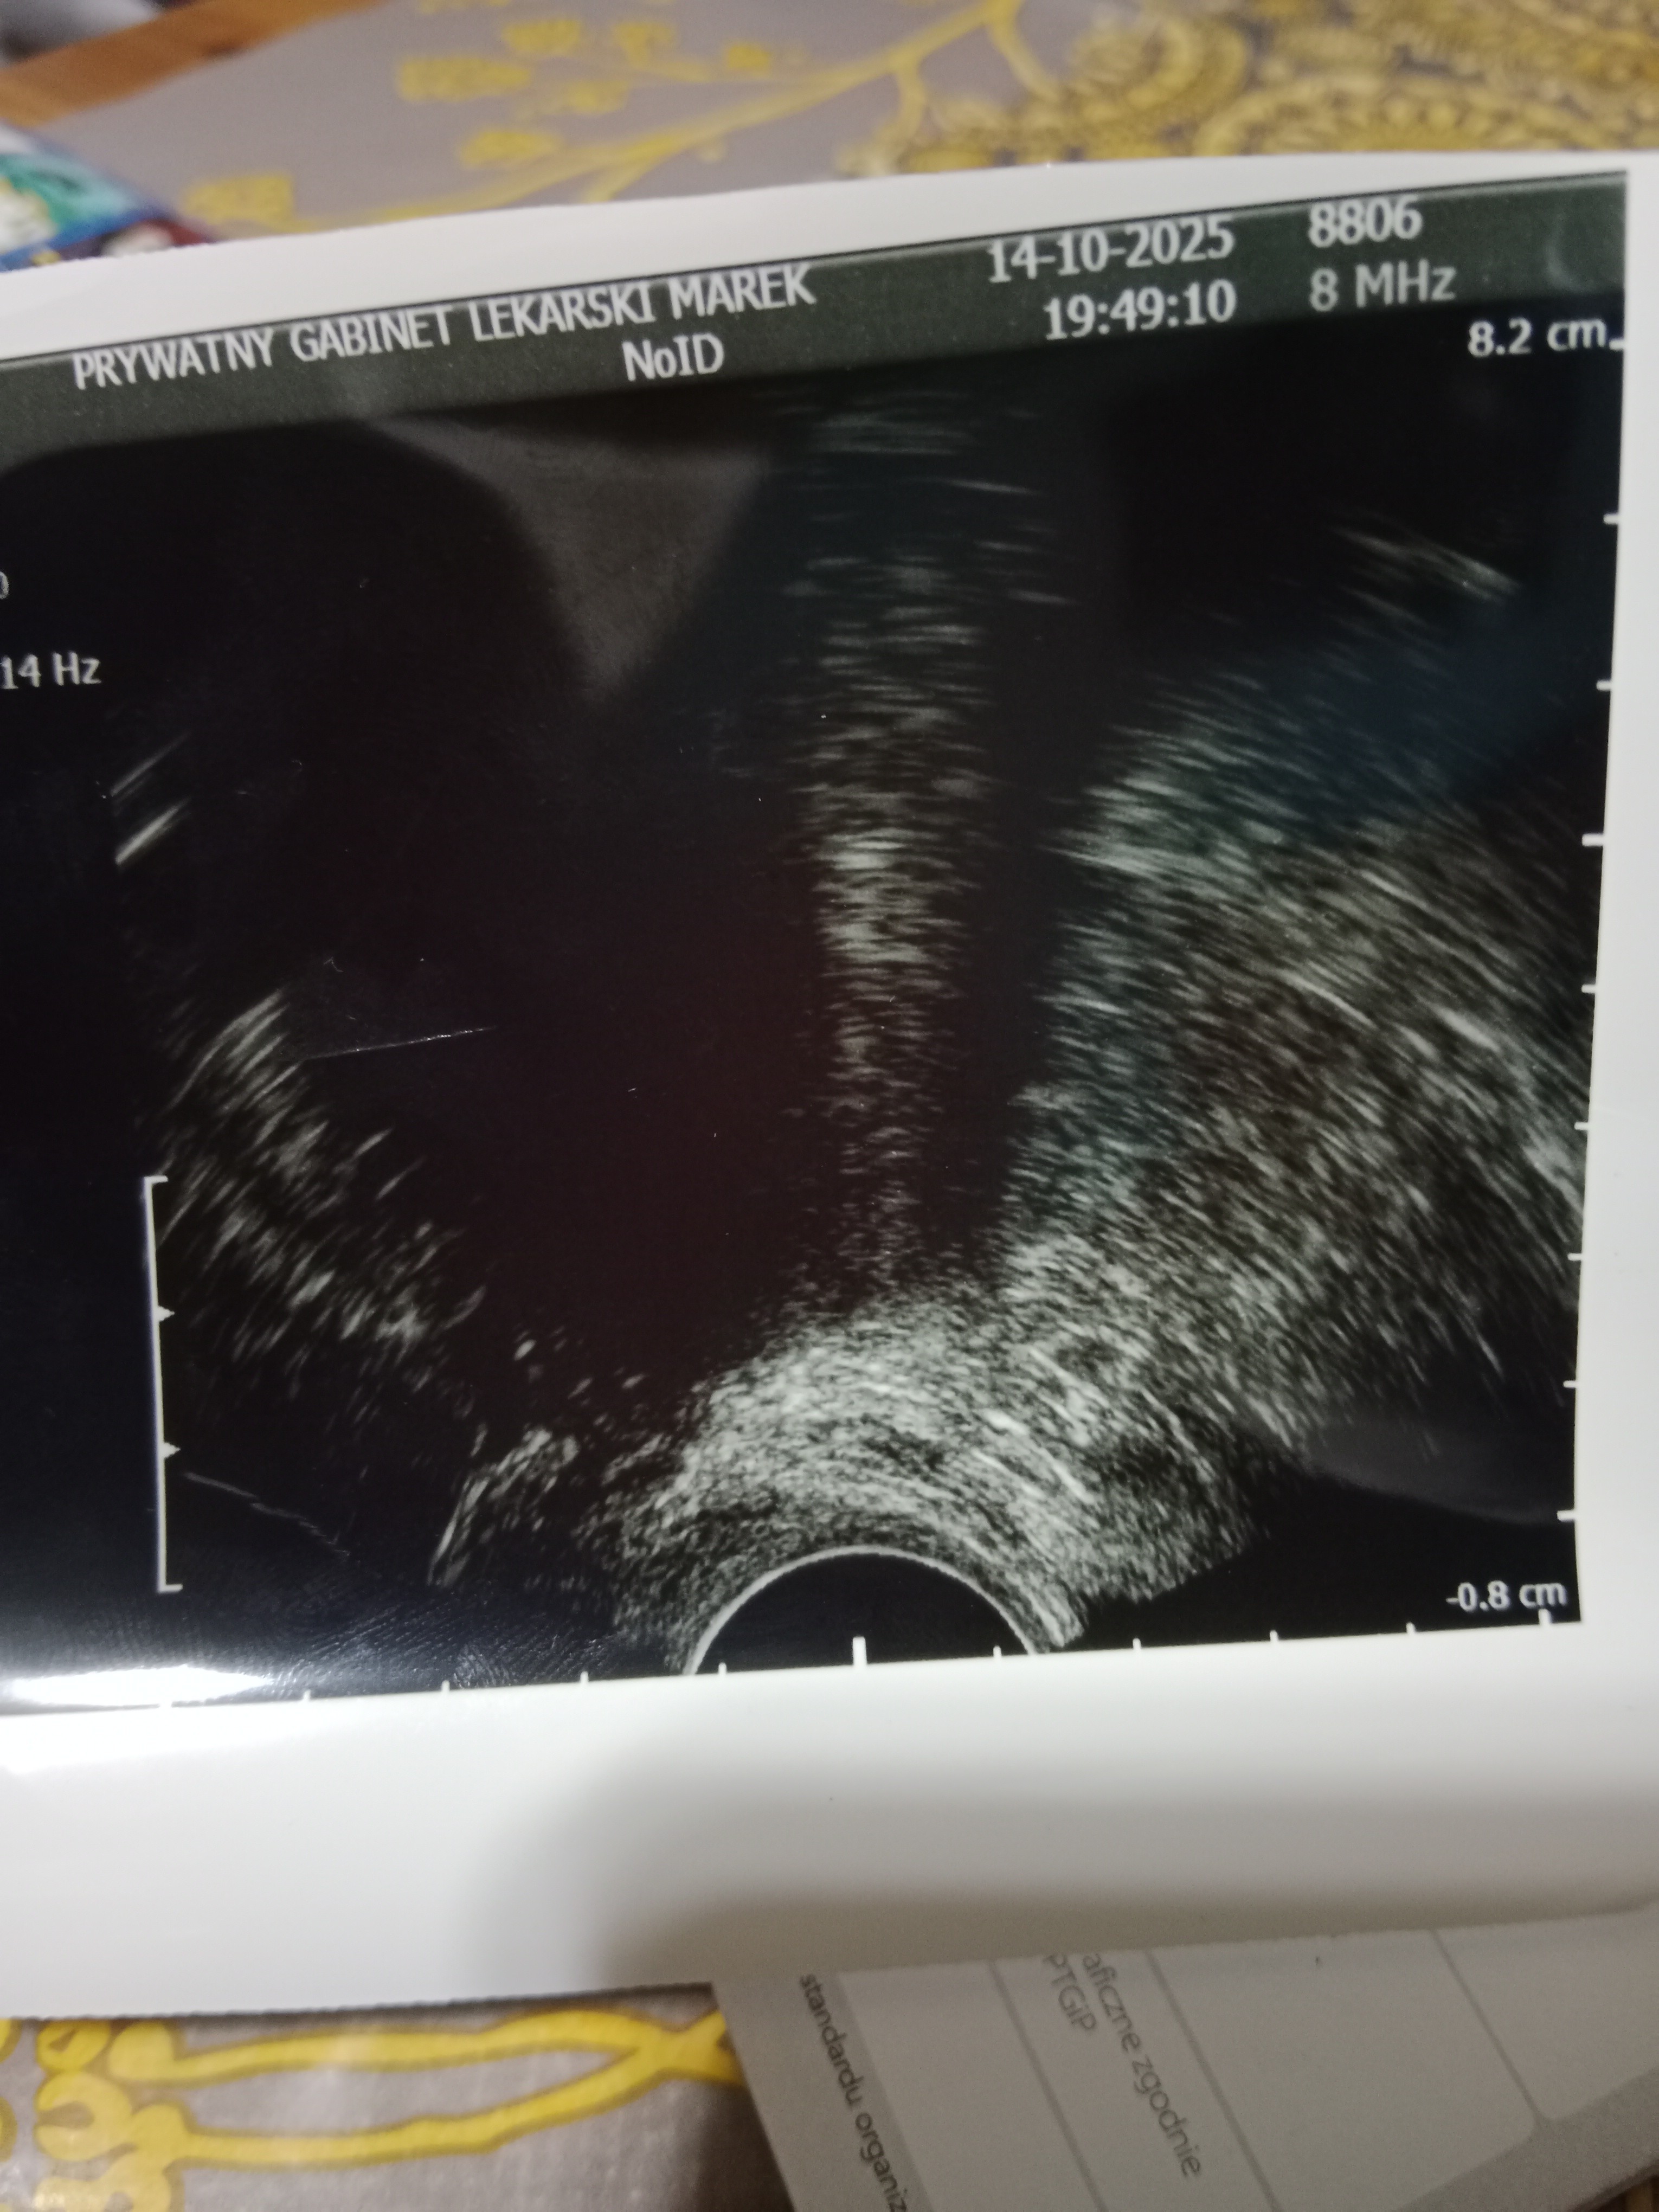

Dziewczyny jestem po wizycie, mamy 7mm pęcherzyk.. Lekarz powiedział, że na ten moment wszystko dobrze wygląda i za tydzień w środę znowu wizyta i USG zobaczymy czy pojawi się zarodek i serduszko..

dostałam luteinę dopochwowo 200mg dwa razy dziennie (wcześniej brałam progesteron besins 200mg ale mocno mi się kręci w głowie po nim) także zmiana na dopochwowy, kamień z serca mi trochę spadł

Mówił, że zaczyna się coś pokazywać powoli no ale tak definitywnie tego jeszcze nie potwierdził, powiedział, że za tydzień będziemy wiedzieć więcej ale uspokajał mnie i mówił, że jego zdaniem wszystko będzie okej, także staram się wierzyć w jego słowaŚwietna wiadomośćmówił lekarz czy jest cialko żółte czy tylko pęcherzyk?